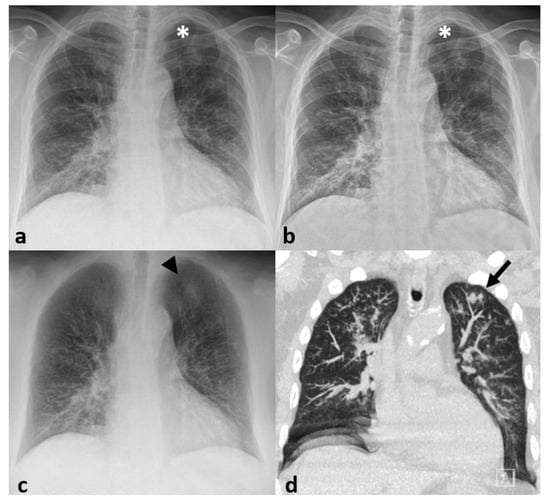

3.3. Imaging Findings